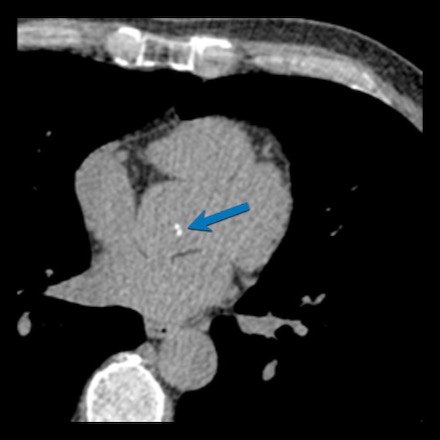

Another example of positive remodeling of a calcified plaque in the proximal LAD.

Again, the plaque is outward from the lumen causing no stenosis in the LAD.